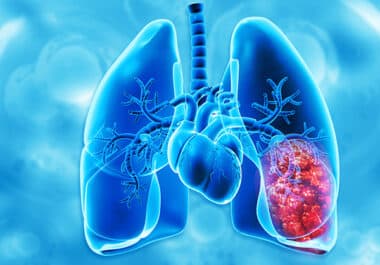

FDA Approves Subcutaneous Formulation of EGFR-targeted Therapy for Non-small Cell Lung Cancer

Patients now have the option of receiving the bispecific antibody amivantamab as an injection. The U.S. Food and Drug...